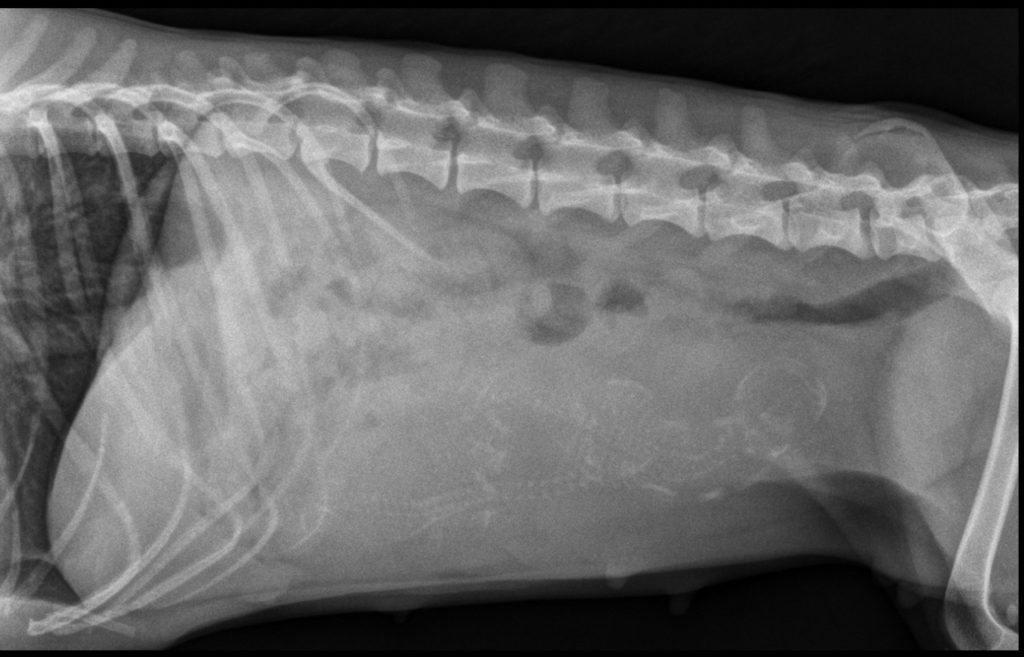

From cliniqueduvieuxpont.fr

Imagerie Médicale Air Dans Intestin Chien Un bruit fort dans le ventre de votre chien, suivi d’une odeur nauséabonde… non, personne n’aime avoir des gaz, même votre. Ils dépendent du type de blocage. On parle d’occlusion ou d’obstruction intestinale lorsque le passage des matières digestives cesse dans une partie ou la totalité. Zoom sur l’occlusion intestinale, ses différentes formes, ses causes, ses manifestations, les traitements envisagés. Air Dans Intestin Chien.